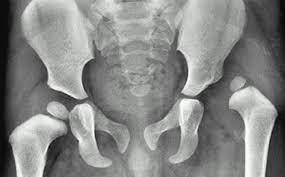

Arthritis is a term for inflammation of the joints and surrounding structures. There are many different types, the most common being osteoarthritis and rheumatoid arthritis, but arthritis also includes puerperosis and fibromyalgia (1). Osteoarthritis (OA) of the hip is a very common problem in Western society. It affects up to 25% of the population over 55 years of age, is more common in women, and genetic and lifestyle factors contribute to its onset, in addition to ageing. (10).

OA is a progressive wear and tear of the cartilage, resulting in bone-on-bone contact, which causes changes in the bone system. Of course, changes in the bone system. Of course, one change affects the other, and the soft-tendinous structures of the hip joint are also affected.

Hip pain that occurs in OA occurs gradually. May radiate forward into the groin or back towards the buttock, thigh or knee. Hip pain at night or at rest after activity is particularly common. It is also characterised by stiffness of the joint in the morning or after prolonged rest.

When patients perform active hip flexion, they feel pain on the outside of the hip. Symptomatology associated with hip pain includes the presence of popping, grinding, bouncing in the hip joint, limping, decreased joint mobility and increased tenderness. In the early stages of the disease, the greatest limitation occurs in abduction and rotation movements, but as the disease progresses, movements in other directions also become limited (1).